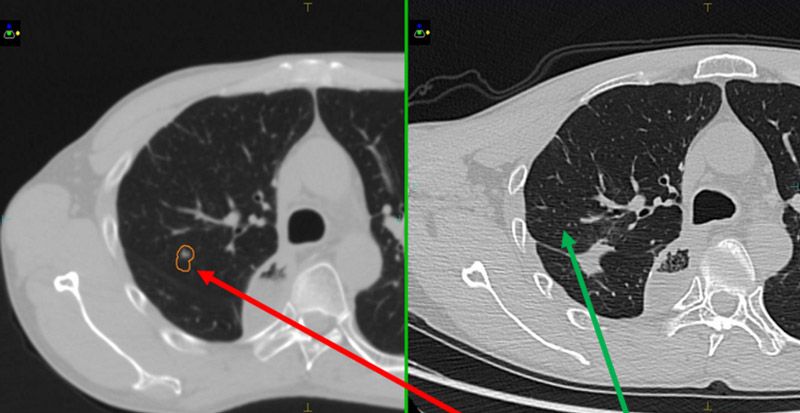

In order to better assess the benefits of mDIBH, CT images were also captured with the patients in free-breathing. The two sets of images (figure 1) were transferred to Monaco version 5.11. Breath-hold details and lung volumes for both patients are shown in table 1.

Plans were evaluated according to TG101 critical structure dose constraints (table 2). With patients in mDIBH, the targets were static. Following discussions between the physicians and physicists, the CTVs were expanded by 5 mm to obtain PTVs (red outline in figures 2 and 3), in order to best protect the surrounding normal tissues. The plans were confirmed by the physician and verified using ArcCheck. The Gamma Analysis pass rate was around 95% (3 mm, 2%).